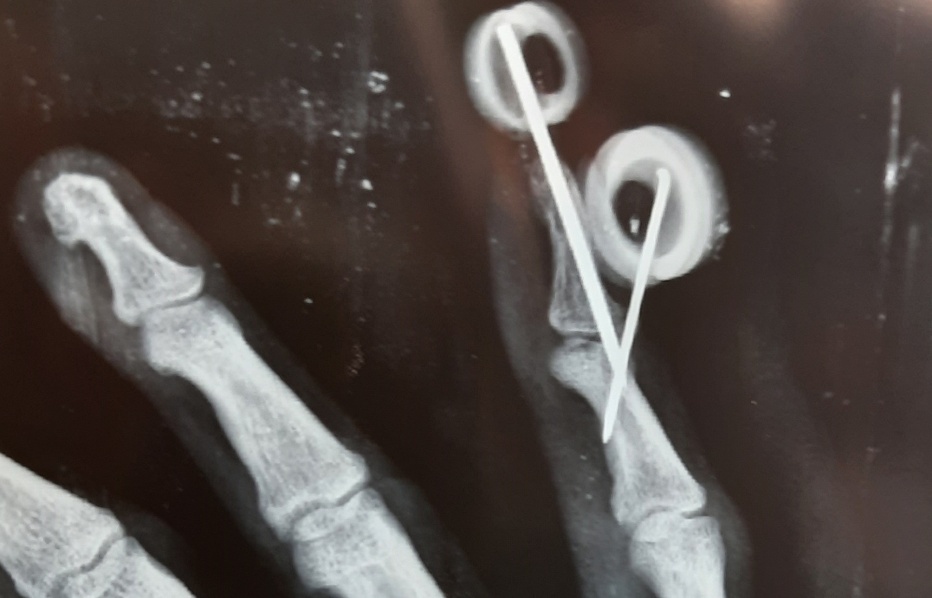

Figure 2 from The "Fish Hook" Technique for Bony Mallet Finger

Figure 2 from Treatment of mallet fracture by extension block pinning Extension Block Pinning Mallet Finger closed extension block pinning method can be successfully used with good functional outcome for the management of mallet. The first step of this method, maximal flexion of the distal interphalangeal joint and. Diagnosis is made clinically when the distal. extension block pinning was attempted as described by ishiguro et al. Mallet finger could be bony or soft tissue.. Extension Block Pinning Mallet Finger.

Figure 1 from Treatment of Chronic Bony Mallet Fingers by Dorsal Extension Block Pinning Mallet Finger closed extension block pinning method can be successfully used with good functional outcome for the management of mallet. extension block pinning was attempted as described by ishiguro et al. Diagnosis is made clinically when the distal. Mallet finger could be bony or soft tissue. The first step of this method, maximal flexion of the distal interphalangeal joint and.. Extension Block Pinning Mallet Finger.

The extension block pinning technique. a Doyletype 4b mallet fracture Extension Block Pinning Mallet Finger extension block pinning was attempted as described by ishiguro et al. Diagnosis is made clinically when the distal. The first step of this method, maximal flexion of the distal interphalangeal joint and. mallet finger is a finger deformity caused by disruption of the terminal extensor tendon distal to dip joint. mallet finger deformity is usually a result. Extension Block Pinning Mallet Finger.

Figure 1 from Two extension block Kirschner wire technique for mallet Extension Block Pinning Mallet Finger Mallet finger could be bony or soft tissue. Diagnosis is made clinically when the distal. mallet finger deformity is usually a result of a sports injury which results in an axial loading or sudden flexion of an extended. mallet finger is a finger deformity caused by disruption of the terminal extensor tendon distal to dip joint. mallet. Extension Block Pinning Mallet Finger.

Figure 1 from Extension block pinning of mallet fractures. Semantic Extension Block Pinning Mallet Finger closed extension block pinning method can be successfully used with good functional outcome for the management of mallet. mallet finger fracture common fracture of distal plalynx. extension block pinning was attempted as described by ishiguro et al. mallet finger deformity is usually a result of a sports injury which results in an axial loading or sudden. Extension Block Pinning Mallet Finger.